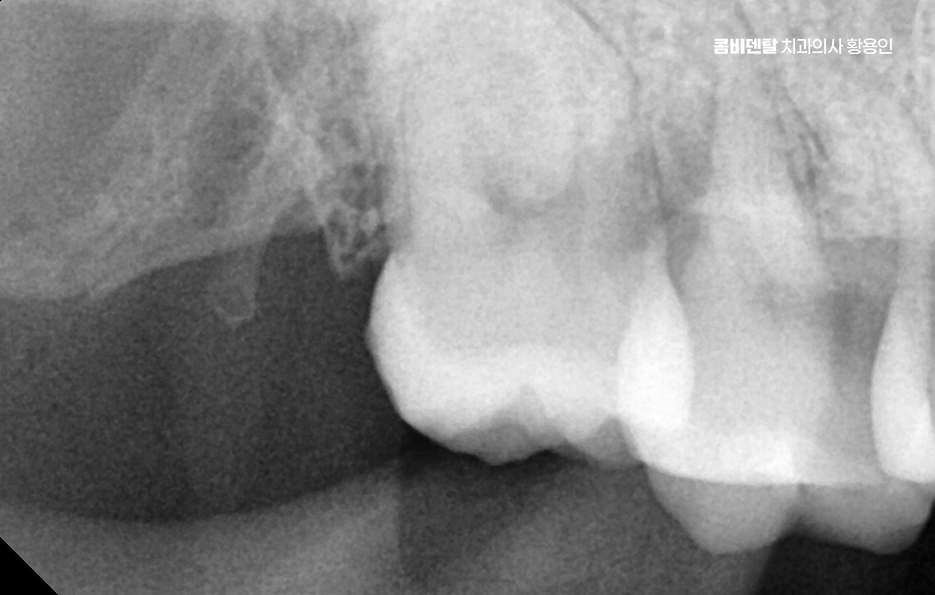

이런 경우에는 염증이 너무 심해지기 전에 빠르게 치과에 내원해서 사랑니 위치와 형태를 확인하는 X-ray 검사를 먼저 진행해야 하고 진단 결과 사랑니가 턱뼈에 수평으로 눌려 있거나, 인접 치아 뿌리를 밀고 있는 형태라면 단순히 약물치료만으로는 해결이 되지 않기 때문에, 염증을 가라앉히고 난 후 발치를 진행하는 방향으로 치료가 이루어지는 경우가 일반적이라 할 수 있어요

또 사랑니가 잇몸 안쪽에서 완전히 매복된 경우에도 사랑니 주변 잇몸 통증에 통증이 생기는 경우가 있는데 겉에서 보이지 않더라도 X-ray 상에서 보면 사랑니가 비스듬히 누워 있거나 옆 치아를 밀고 있는 경우가 많은데 이런 매복 사랑니는 염증이 없더라도 조용히 인접 치아의 뿌리를 괴사시키거나 인접면 충치를 유발하기도 해서 통증이 발생하지 않더라도 예방적 발치를 권유받는 경우도 있고 통증이 시작된 후에는 주변 뼈 흡수나 치주염, 잇몸 괴사로 진행될 가능성도 있기 때문에 사랑니 발치 판단을 적절히 세울 필요가 있어요